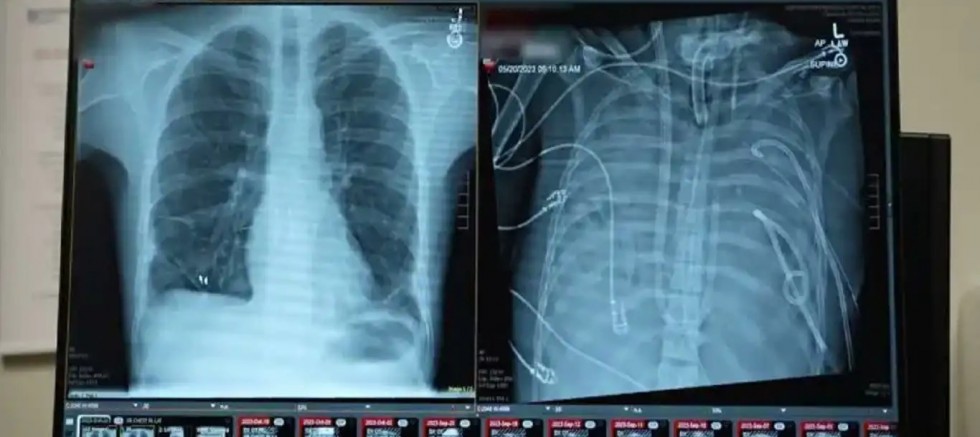

Cerrahlar, akciğerleri geri dönüşü olmayan şekilde hasar gören bir hastayı, organ nakli yapılana kadar yapay akciğer sistemiyle 48 saat boyunca hayatta tutmayı başardı. Yeni sistemin, kalpten geçen kan akışını sürdürürken kana oksijen sağlayabildiği bildirildi.

Tıp dergisi Med’de 29 Ocak’ta yayımlanan çalışmaya göre, doktorlar kanı oksijenlendiren ve kalp dolaşımını destekleyen şantlar, tüpler ve pompalarla özel bir sistem geliştirdi. Uzmanlar, bunun gerçek anlamda bir yapay akciğerin, uygun donör bulunana kadar hastayı yaşatabileceğini gösterdiğini belirtiyor.

Bunun üzerine cerrahlar, hastanın hastalıklı akciğerlerini tamamen çıkararak geliştirdikleri yapay akciğer sistemine bağladı. Sistem, kalbin sağ tarafından alınan kanı bir pompadan geçirerek oksijen ekliyor ve karbondioksiti uzaklaştırıyor, ardından kanı kalbin sol tarafına yönlendirerek vücuda pompalanmasını sağlıyor. Böylece hem kalbin normal işlevi korunuyor hem de dokulara oksijen ulaştırılıyor.

Daha önce doktorlar, ekstrakorporeal membran oksijenasyonu (ECMO) adı verilen dış destek sistemini kullanarak, nakil bekleyen bazı hastaları akciğersiz olarak hayatta tutmuştu. Ancak Bharat, ECMO’nun kalp için yeterli kan akışını sağlamadığı için gerçek anlamda bir yapay akciğer olmadığını ifade etti.